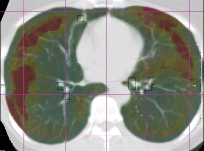

() Ground truth

Refer to caption

(a) Predicted error

(b) Magnification of (a)

(c) Magnification of (b)

Figure 5: Example data from the SPREAD dataset. The left column (a,c) shows the fixed image with the ground truth registration error overlaid in color. The square boxes around each landmark are given the same error as the error at the landmark. The right column (b,d) shows the moving image after registration with the registration error predicted by the proposed method overlaid in color. (c) and (d) are zoomed in versions of (a) and (b).